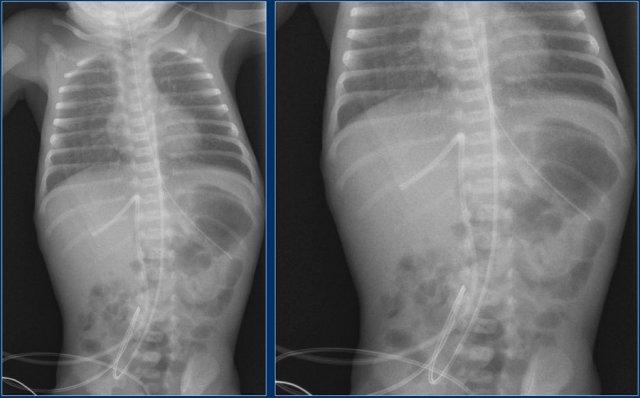

Đường truyền động mạch rốn (3)

Hãy quan sát kỹ hình ảnh trước.

Sau đó tiếp tục đọc.

Các phát hiện bao gồm:

- Đặt sai vị trí đường truyền động mạch rốn, bị gấp khúc trong lòng động mạch chủ bụng.

Đường truyền động mạch rốn (4)

- Đường truyền động mạch rốn ở vị trí quá sâu, đầu catheter nằm tại quai động mạch chủ.

- Đường truyền tĩnh mạch rốn với đầu catheter nằm trong nhánh tĩnh mạch cửa phải.